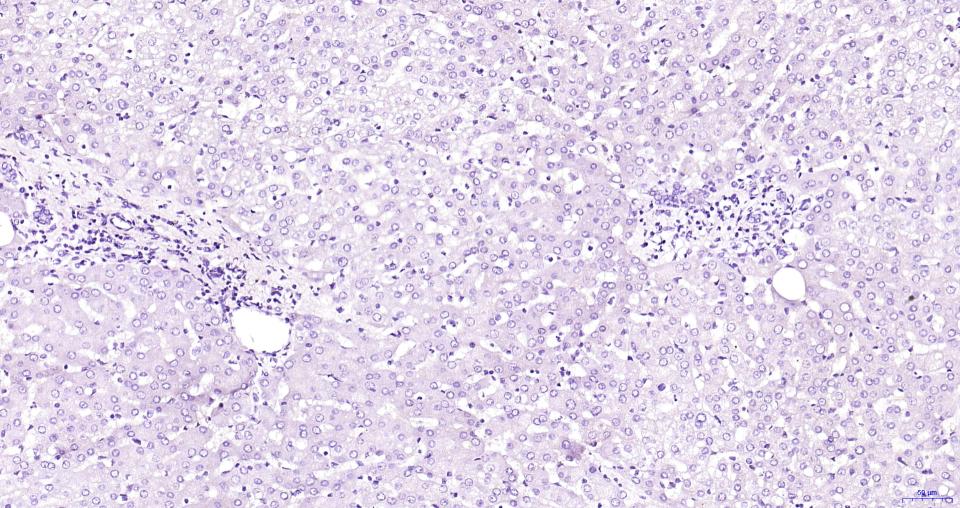

Paraformaldehyde-fixed, paraffin embedded Human Brain; Antigen retrieval by boiling in sodium citrate buffer (pH6.0) for 15 min; Antibody incubation with TAC1 Monoclonal Antibody, Unconjugated (bsm-61420R) at 1:200 overnight at 4°C, followed by conjugation to the bs-0295G-HRP and DAB (C-0010) staining.

(Negative control)Paraformaldehyde-fixed, paraffin embedded Human Brain; Antigen retrieval by boiling in sodium citrate buffer (pH6.0) for 15 min; Antibody incubation with TAC1 Monoclonal Antibody, Unconjugated (bsm-61420R) at 1:200 overnight at 4°C, followed by conjugation to the bs-0295G-HRP and DAB (C-0010) staining.